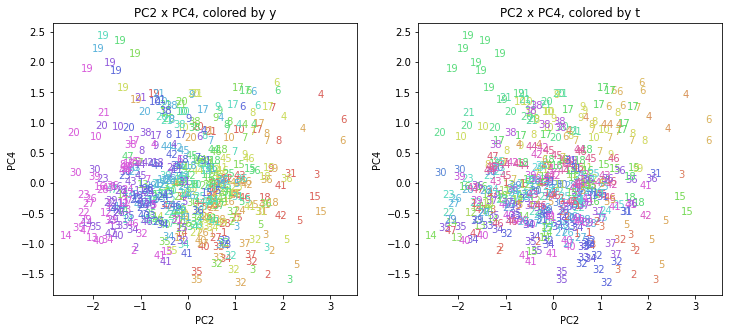

PCAの結果の第n主成分をPCnと表記します。

医療費データの場合と同様に、PCAの結果を見やすく表示するため、seabornのカラーパレットを使って、年月別、都道府県別に色分けして図示してみます(左側が年月別に色分け、右側が都道府県別に色分け)。PC1~PC8まで表示しました。

都道府県番号の表示

上の色分けだけでは都道府県が区別しにくいので、医療費データの場合と同様に、点の代わりに都道府県番号をプロットした図も描いておきます(色分けは上と同じ)。

医療費データの場合ほどはっきりとはしていませんが、PC2が概ね時間の経過を表す成分で、残りの成分が時点によって変わらない地域の特徴を表す成分となっているようです。

また、PC1×PC3を見ると、47沖縄が他の都道府県からかなり離れたところに位置しており、沖縄の地域差が際立っているのが分かります。これは、以前別の記事で年齢階級のない健診データでPCAを実行した場合と似た結果となっています。